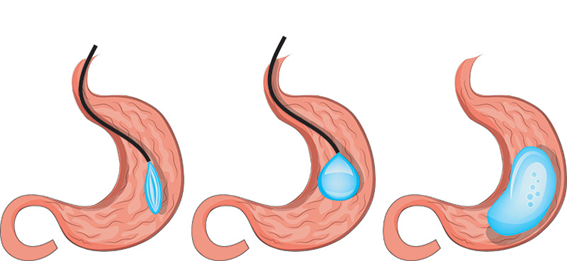

Passagem de Balão Intragástrico

1. O balão intragástrico é introduzido desinsuflado durante a endoscopia e colocado no estômago.

2. Um líquido azul (azul de metileno diluído em soro fisiológico) é colocado dentro do balão através de uma válvula. O volume varia entre 500-700 ml.

3. O aparelho de endoscopia é removido e o balão intragástrico pode ser deixado por um período de até 6 meses.

Como funciona o balão intragástrico?

O balão intragástrico ocupa um espaço dentro do estômago e o paciente fica com sensação de plenitude e saciedade precoce. Em outras palavras, sobra menos espaço para os alimentos, diminuindo o volume ingerido nas refeições.

Durante o período de tratamento, é essencial um acompanhamento multidisciplinar que permita reeducação alimentar e mudança do estilo de vida, garantindo assim o sucesso e a manutenção da perda de peso após a retirada do balão.